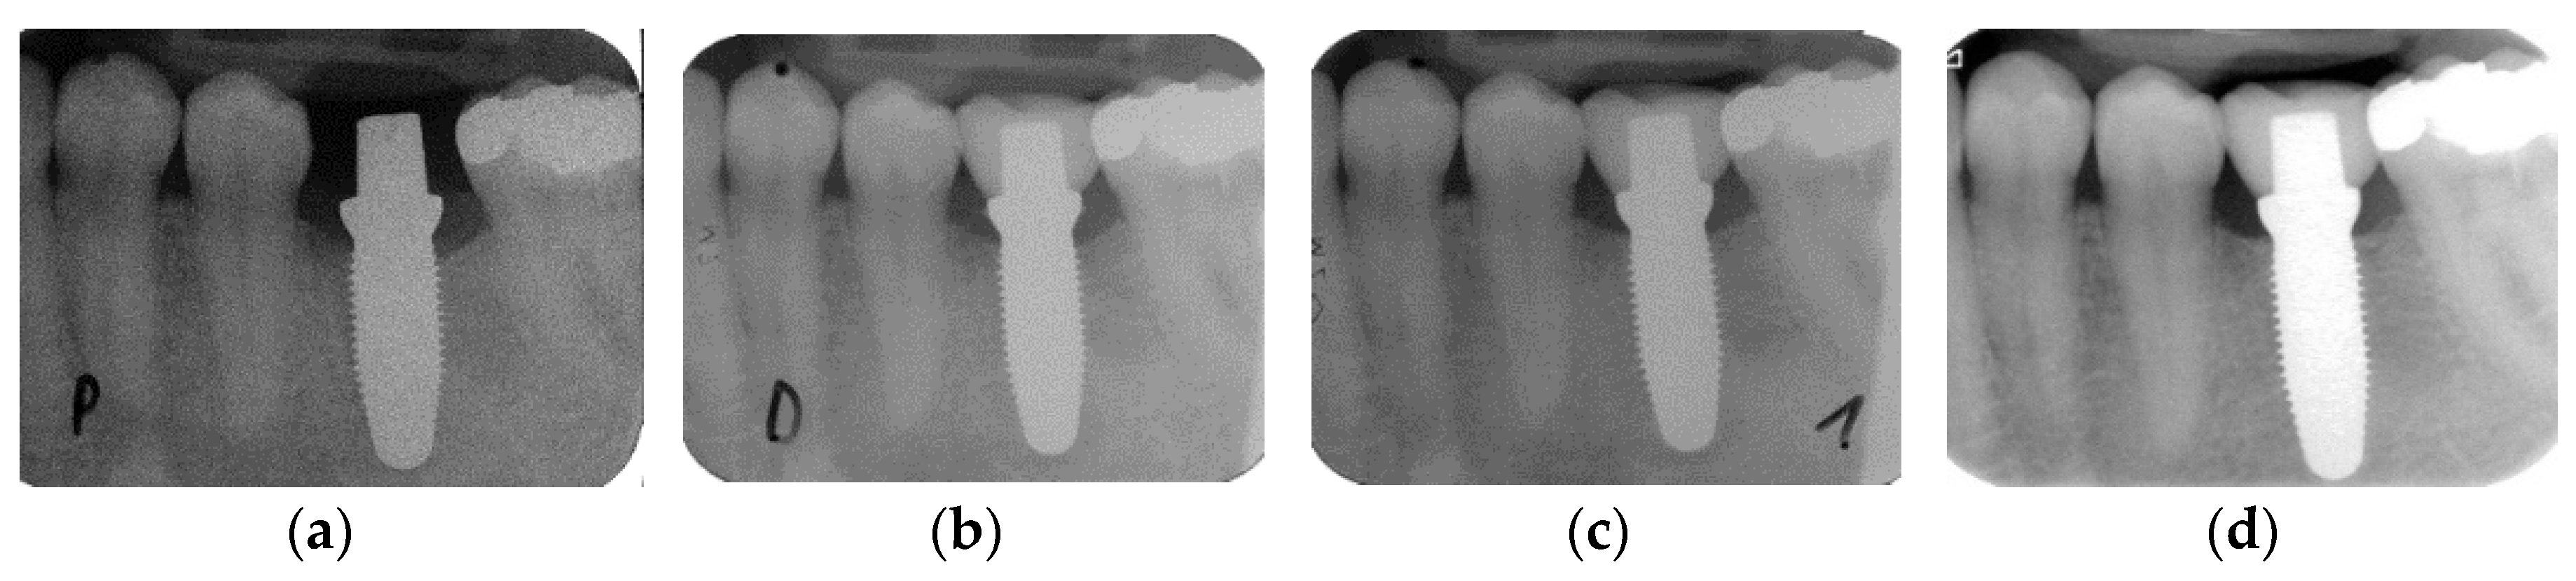

The marginal bone loss from implant installation to the 5-year follow-up for all implants is depicted in Figure 1a. The bone loss from implant insertion until the reconstruction delivery was 0.71 mm (± 0.67), 0.78 mm (± 0.67) at the 1-year follow-up and 0.81 mm (± 0.77) at the 5-year recall. The bone loss from implant installation to the delivery was statistically significant (p < 0.001), while the loss from the prosthetic delivery to the 1-year (p = 0.548) and to the 5-year follow-up (p = 0.611) was not (Table 2). Four implants showed bone loss >2 mm at 5 years. Two implants had already an increased bone of >2 mm loss at 1 year, and their situation was stable up to 5 years. The other two implants showed an increase in radiographically measured bone loss of approximately 1 mm over the time interval of 4 years. Conventional maintenance on a regular basis stabilized the situation. From implant insertion to the 5-year follow-up, five implants (10.4%) gained bone, whereas four implants (8.3%) lost > 2 mm (Table 3). None of the implants lost more than 3 mm of bone. Hence, when applying the success and failure criteria according to Östman et al. [30], 91.7% of the remaining implants were successful according to criteria I and 100% were successful according to criteria II. A bone loss difference was observed between implants used for SC and implants used for FDP up to the 5-year follow-up (Figure 1b). The bone loss at prosthetic delivery was 1.03 mm (±0.71) for the FDPs and 0.41 mm (±0.48) for the SCs (p = 0.001). At the 1-year follow-up, the marginal bone reduction was 1.08 mm (±0.67) for the FDPs and 0.48 mm (±0.54) for the SCs (p = 0.001). At the 5-year follow-up, the FDPs showed a bone loss of 1.14 mm (±0.71) and the SCs showed a bone loss of 0.41 mm (±0.68) (p = 0.001). In the univariate analysis (Table 4) of the baseline variables gender, jaw, position in the jaw, implant diameter and length, bone quality and quantity, anchorage, grafting and flap design, no significant influence on bone loss could be found. Figure 2 presents exemplary follow-up radiographs of an SC.

Figure 2.

Standardized radiographs for the assessment of marginal bone loss (MBL): (a) implant insertion; (b) prosthetic delivery; (c) one-year follow-up; (d) five-year follow-up.